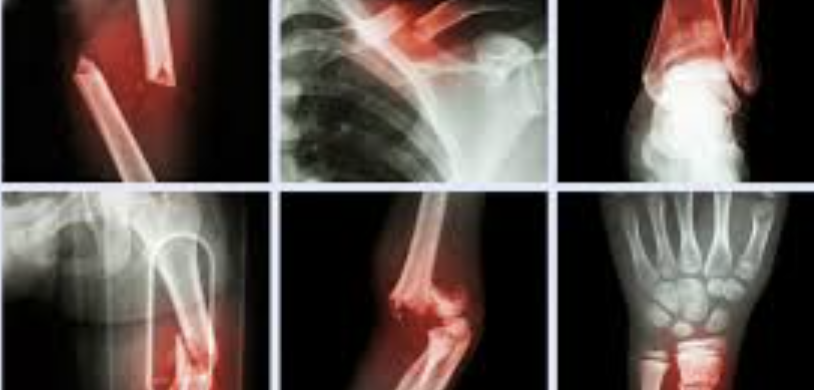

GLUTATION y FRACTURAS

El glutatión puede desempeñar un papel importante en el proceso de curación de fracturas debido a sus propiedades antioxidantes y su capacidad para reducir el estrés oxidativo, que es un factor clave en la reparación del tejido óseo. Aquí te detallo algunos beneficios potenciales del glutatión en este contexto: